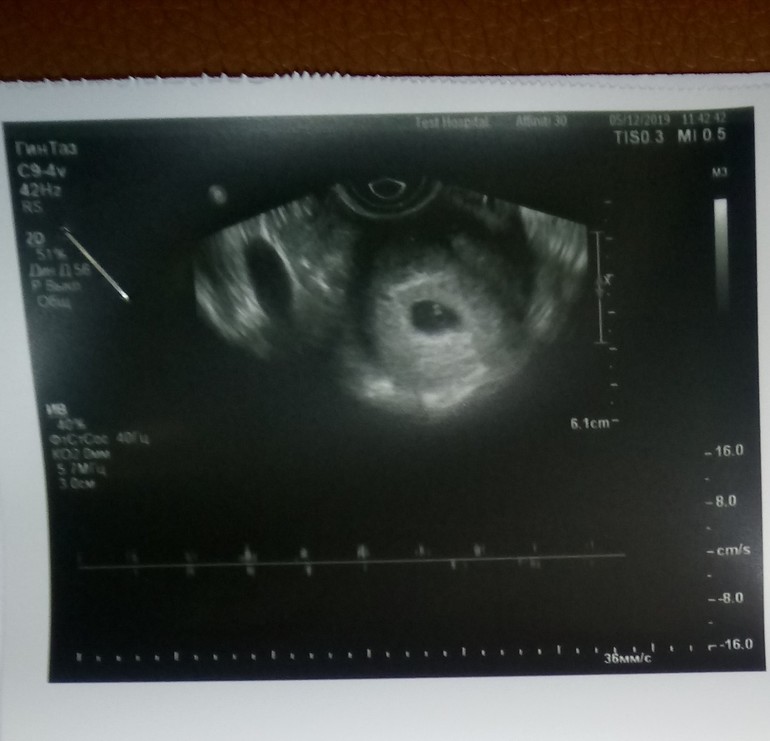

Узи на 21 дпп

21 дпп ещё рано для эмбриона, редко у кого на таком сроке видно. А судя по фото жм есть, так что повторите узи через 7-10 дней и послушаете сердечко.

Думаю нужно повторить УЗИ через неделю. Если есть возможность смените узиста. Эмбриончик виден!,🤞

Это вроже жм. Если есть жм появится и эмбриончик)

Видно эмбрион!